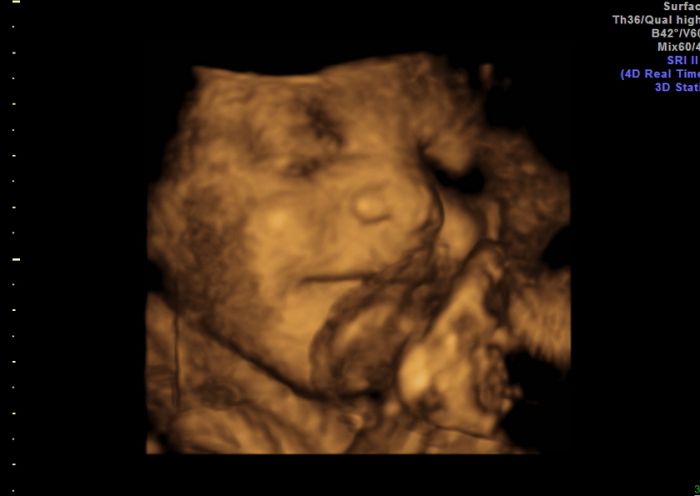

Já je přikládám

pindíka našeho

a na druhé a třetí fotce má před pusinkou pupečník, ale usmíval se na nás šmudlík malej náš

Jani Jeníček je krásný moc hezky se usmívá na té poslední fotečce